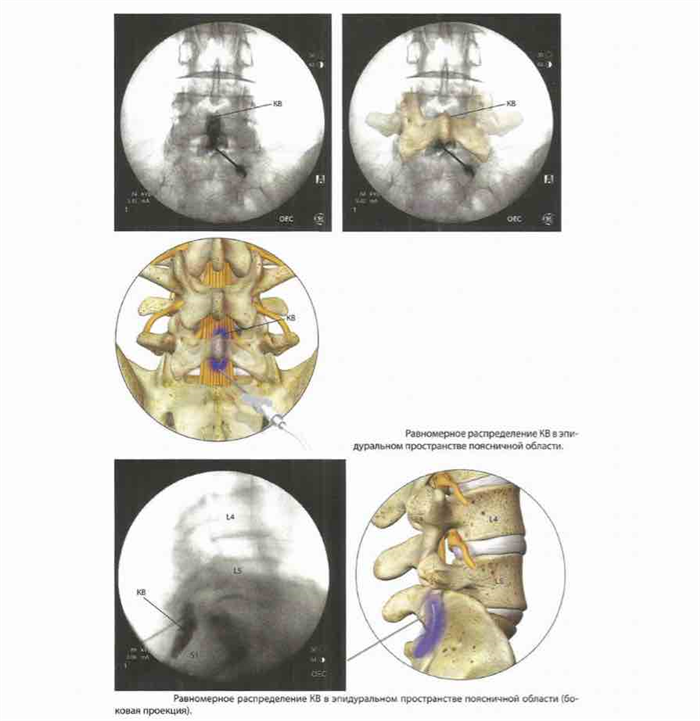

Затем к игле присоединяют шприц объемом 3 мл с трубкой, через которую вводят КВ.

Трубка используется для того, чтобы рука оператора не перекрывала рентгеновский снимок во время введения контрастного вещества (КБ) и для защиты от радиации. КБ должно равномерно распределяться.

Контроль также можно вести через боковую проекцию. Шприц с КБ отсоединяется от трубки, и вместо него подключается шприц объемом 10 мл с сочетанием физиологического раствора и кортикостероида.